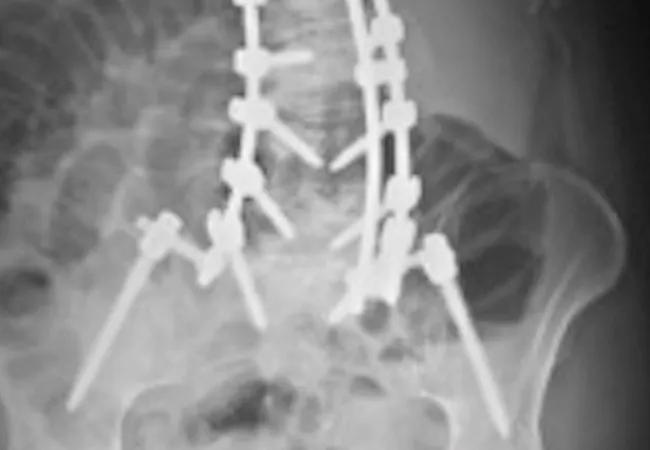

We performed this six-hour procedure using a posterior approach. The spine was exposed from T4 to the sacrum. We then performed a decompression from L1 to L5 to address her spinal stenosis. Posterior column osteotomies (complete facet resections) at L1-L2, L2-L3, L3-L4 and L4-L5 helped mobilize the arthritic spine. Pedicle screw instrumentation was placed from T4 to the sacrum, and we used iliac fixation to strengthen the construct. Various maneuvers were used to correct the severe deformity, and then cobalt chrome rods were placed to hold the correction (Figures 2A, B).

16-ort-1787-savage-inset-image-02-pairing-650pxl-width

Figures 2A and B: Postoperative radiographs reveal correction of the deformity with restoration of normal alignment.